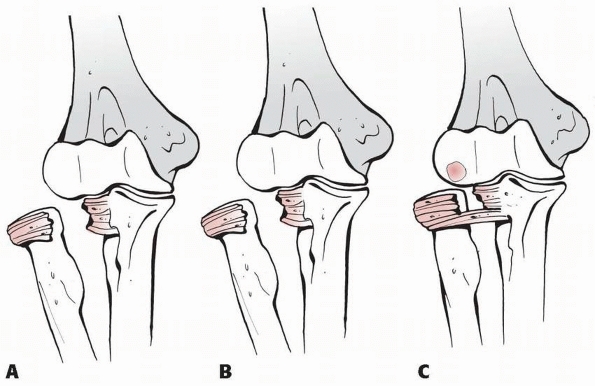

![]() |

FIGURE 12-23 A. Radial head dislocation and complete annular ligament tear. B. Radial head dislocation and partial ligament tear. C. Radial head dislocation and partial or complete annular ligament tear and osteochondral fragment.